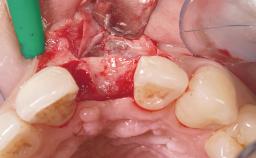

Late Flapless Placement of an Implant in a Maxillary Left Central Incisor Site

A 39-year-old male patient presented with a chief complaint of discomfort and gingival discoloration around his maxillary left central incisor. He was in good general health and was a non-smoker. His past dental history was significant because of the traumatic fracture of tooth 21 in a sporting accident at age 13. Initial dental treatment included endodontic therapy and a full-coverage restoration. The patient became symptomatic 5 years later, when structural failure of the tooth resulted in the dislodgment of the crown. Endodontic retreatment, apical surgery, and post-and-core restoration were performed.

Bone Augmentation Horizontal|Staged

Soft Tissue Grafting Simultaneous